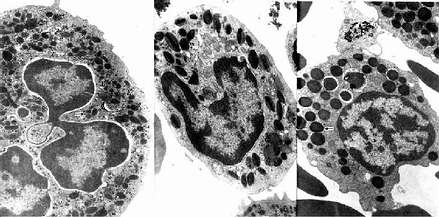

中性粒细胞的胞质染成粉红色,含有许多细小的淡紫色及淡红色颗粒,颗粒可分为嗜天青颗粒和特殊颗粒两种。嗜天青颗粒较少,呈紫色,约占颗粒总数的20%,光镜下着色略深,体积较大;电镜下呈圆形或椭圆形,直径0.6~0.7μm,电子密度较高(图5-4,5-5),它是一种溶酶体,含有酸性磷酸酶和过氧化物酶等,能消化分解吞噬的异物。特殊颗粒数量多,淡红色,约占颗粒总数的80%,颗粒较小,直径0.3~0.4μm,呈哑铃形或椭圆形,内含碱性磷酸酶、吞噬素、溶菌酶等。吞噬素具有杀菌作用,溶菌酶能溶解细菌表面的糖蛋白。

2.嗜酸性粒细胞 嗜酸性粒细胞(eosinophilicgranulocyte,eosinophil)占白细胞总数的0.5%-3%。细胞呈球形,直径10~15μm,核常为2叶,胞质内充满粗大(直径0.5~1.0μm)、均匀、略带折光性的嗜酸性颗粒,染成桔红色(图5-2)。电镜下,颗粒多呈椭圆形,有膜包被,内含颗粒状基质和方形或长方形晶体(图5-4,5-5)。颗粒含有酸性磷酸酶、芳基硫酸酯酶、过氧化物酶和组胺酶等,因此它也是一种溶酶体。

3.嗜碱性粒细胞 嗜碱性粒细胞(basoophilic granulocyte,basophil)数量最少,占白细胞总数的0~15。细胞呈球形,直径10-12μm。胞核分叶或呈S形或不规则形,着色较浅。胞质内含有嗜碱性颗粒,大小不等,分布不均,染成蓝紫色,可覆盖在核上(图5-2)。颗粒具有异染性,甲苯胺蓝染色呈紫红色。电镜下,嗜碱性颗粒内充满细小微粒,呈均匀状或螺纹状分布(图5-4,5-5)。颗粒内含有肝素和组胺,可被快速释放;而白三烯则存在于细胞基质内,它的释放较前者缓慢。肝素具有抗凝血作用,,组胺和白三烯参与过敏反应。嗜碱性粒细胞在组织中可存活12-15天。

图5-4 三种粒细胞超微结构模式图

图5-5 人三种粒电镜像 ×17800

左图:中性粒细胞(白求恩医科大学尹昕、朱秀雄教授供图)

中图:嗜酸性粒细胞 左图:嗜碱性粒细胞

↑特殊颗粒,(